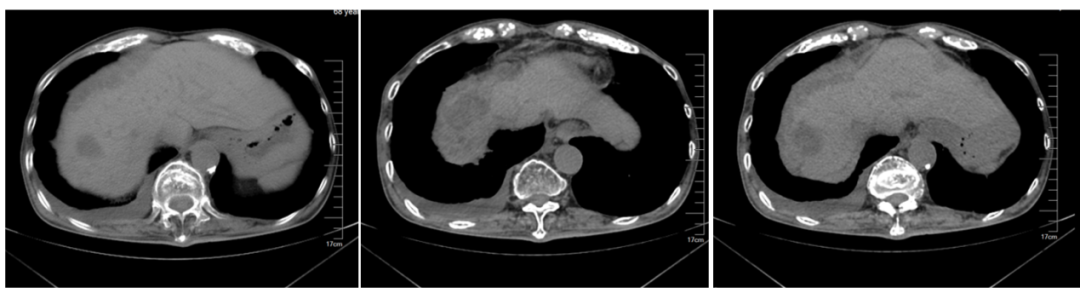

影像学评估:

图14、一线治疗期间影像学评估:左(2018-10-22)、中(2018-12-26)、右(2019-03-26)

第三阶段:二线治疗(2019-12至2020-10)

治疗方案:FOLFOX+贝伐珠单抗*12周期。

最佳疗效:SD

图17、二线治疗期间,疾病稳定:左(2020-04-08)、中(2020-06-19)、右(2020-08-21)